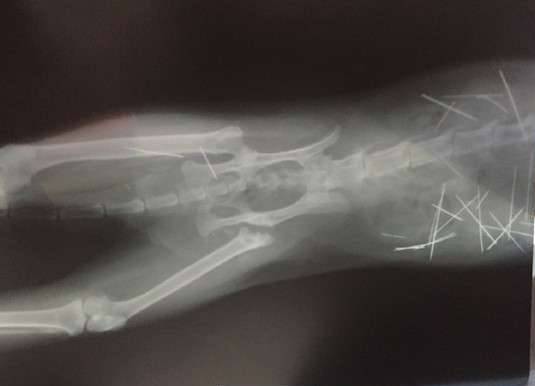

▼这次动物医院连续照了53次X光片,发现猫咪体内有多根细针,有些已经生鏽。

▼其中7根针在皮肤和肌肉、3根针和2根断针在胸腔心脏旁边,30根针在腹腔,其中有4根是插入到左侧肾脏。

▼现在这些针已经开始游离,猫咪很痛苦。医生表示手术也只能取出2/3。

从X光片可以看到,猫咪体内布满密密麻麻的细针,看起来怵目惊心。一年多来,猫咪一直忍受针刺的痛苦,牠无法说话,只能默默承受。在热心人士的帮忙协助下,猫咪终于做完手术,希望牠能够快点好起来,不要再遭遇这样可怕的事。分享出去,让大家都看到吧。